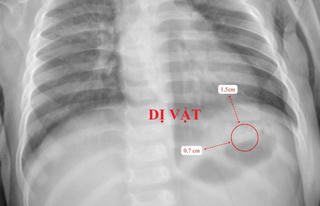

Bé 10 tháng tuổi suýt thủng ruột vì nuốt điếu thuốc lá có mảnh kim loại